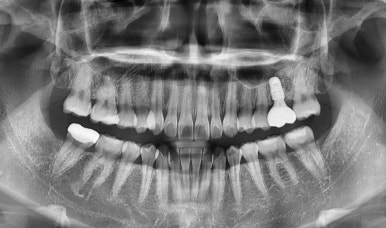

임플란트 픽스처 식립 후와 보철물까지 올라가 완성된 상태의 사진

(좌) 2023-02-15 (우) 2023-05-13

환자분께서 바쁘셔서 올해 2월에 다시 내원을 해주셨고,

뼈가 잘 생성되어 바로 수술이 가능해 임플란트 픽스처를 식립하게 되었습니다.

수술 후 약 3개월이 지나고 뼈와 임플란트가 잘 유착되어 최종적으로 크라운까지 올려 마무리했습니다.